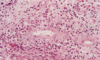

Traumatic fat necrosis

Fat necrosis with lipid-laden macrophages and PMNs